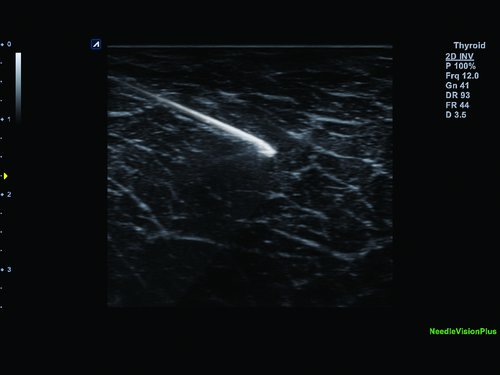

• Elastographie, Panoramic Imaging, Needle Vision (Nadelvisualisierung), Needle Vision Plus (Spezialfunktionen)